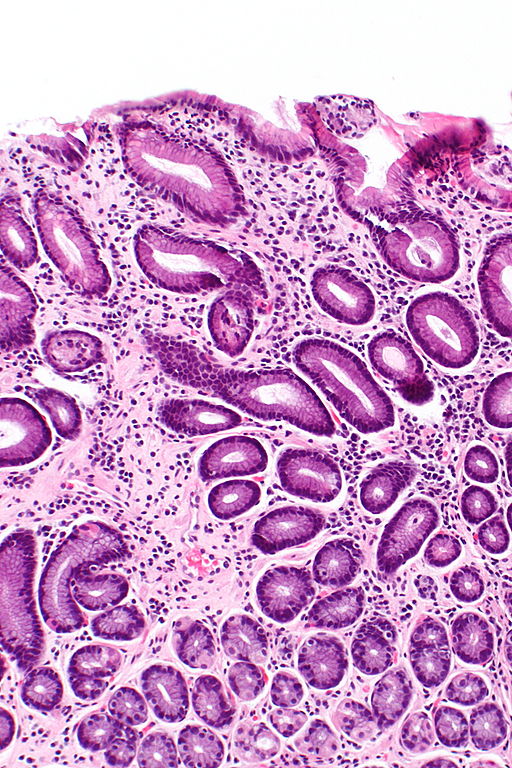

Gastritis is a general term for a group of conditions with one thing in common: Inflammation of the lining of the stomach. Research indicates, Gastritis is when your stomach lining gets red and swollen (inflamed). Evidence suggests, Explore what causes gastritis, how it’s diagnosed, the different types, and which treatments can help reduce inflammation and prevent complications. Analysis reveals, Weakness in your stomach lining allows digestive juices to damage and inflame it, causing gastritis. These findings regarding Gastritis Symptoms Causes Treatments And More provide comprehensive context for understanding this subject.

Gastritis is when your stomach lining gets red and swollen (inflamed). Your stomach lining is strong. In most cases acid does not hurt it. But it can get inflamed and irritated if you drink too much alcohol, …

Mar 20, 2023 · Weakness in your stomach lining allows digestive juices to damage and inflame it, causing gastritis. Learn more about causes, diagnosis, and treatment.

Dec 20, 2017 · Gastritis (acute and chronic) is inflammation of the stomach lining. Learn the causes, symptoms, diagnosis, treatment, home remedies, medications, and diet of acute and chronic gastritis.